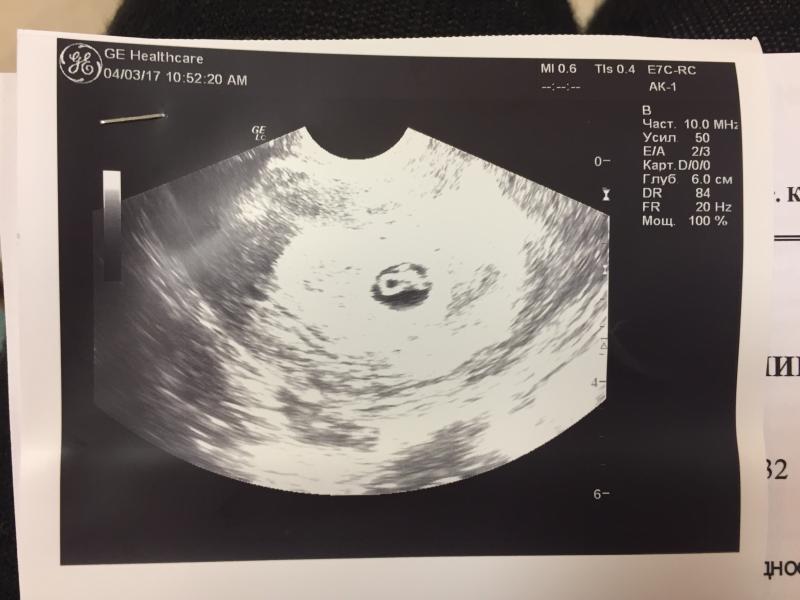

Вот он/она !!! Сказали сердцебиение есть, но послушать не дали. КТР - 0,56 см. Мы совсем крохи - это нармально? Срок - седьмая неделя. Протокол закрыли - куда теперь? Что делать?